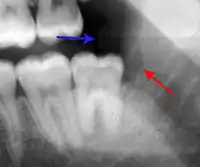

Decay (green) with apical abscess (blue)

The periodontal ligament becomes inflamed and there may be pain when biting or tapping on the tooth. On an X-ray, bone resorption appears as a radiolucent area around the end of the root, although this does not manifest immediately.[10]: 228 Acute apical periodontitis is characterized by well-localized, spontaneous, persistent, moderate to severe pain.[6]: 125–135 The alveolar process may be tender to palpation over the roots. The tooth may be raised in the socket and feel more prominent than the adjacent teeth.[6]: 125–135

- Radiographs utilized to find dental caries and bone loss laterally or at the apex.